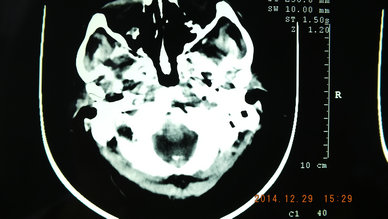

CT49664:脑部肿瘤?

男,55岁,间断性头痛头晕两年,加重一月。 请各位大侠帮忙看下。由于庙小没有增强。谢谢啦!

转移瘤

病史太长,还是考虑原发占位可能性大一点

转移瘤首先考虑,多发腔梗。

考虑转移瘤

首先考虑转移瘤。其次考虑胶质瘤。

多发性腔隙性脑梗塞、右侧大脑镰旁占位不排除,建议行MRI。

多发性腔隙性脑梗塞、右侧大脑镰旁占位、多考虑胶质瘤

1、右枕叶脑梗塞。

2、多发腔梗。